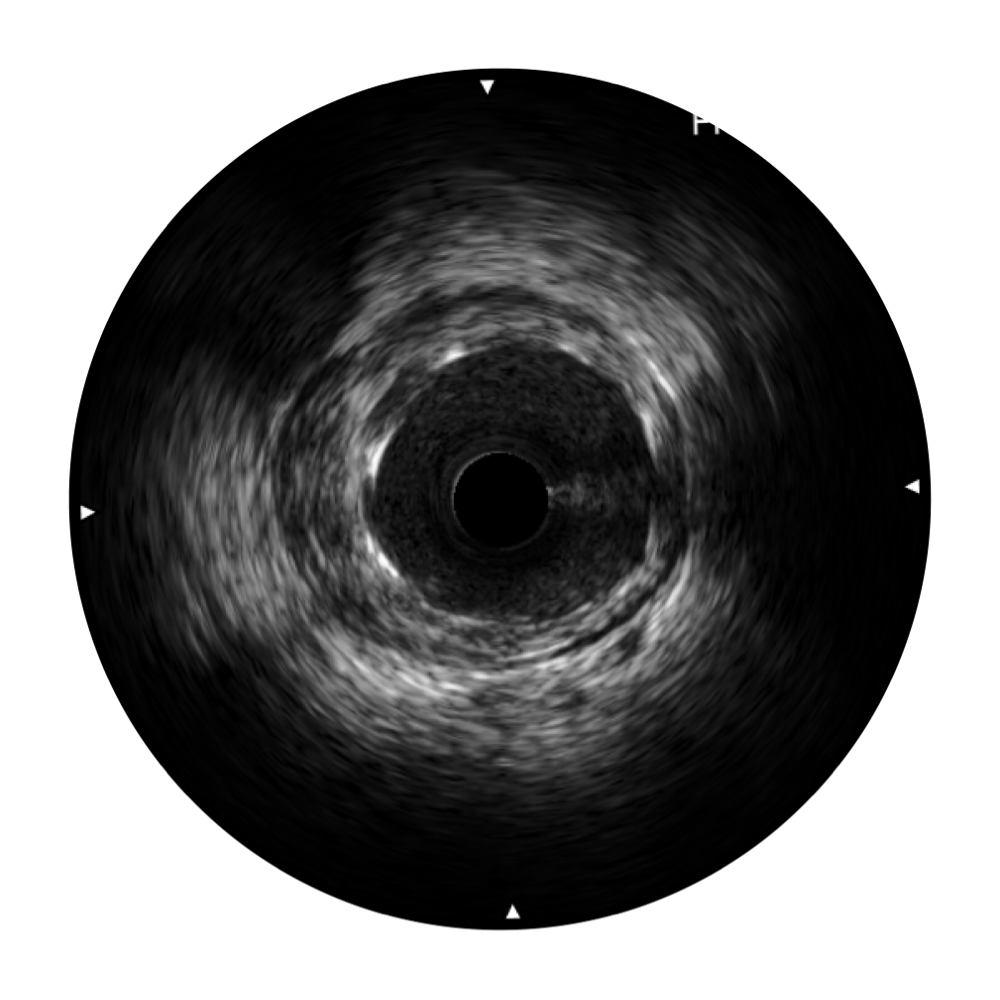

哈哈体育官网宽频IVUS图像

传统IVUS图像

对比传统IVUS导管成像,哈哈体育官网宽频IVUS图像的近场支架梁显影更细腻,远场中膜外血管仍清晰可辨,兼顾远中近,兼顾分辨力与穿透深度